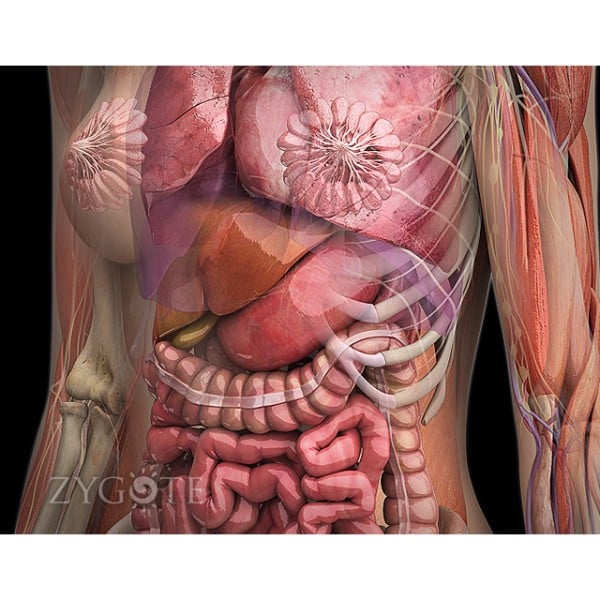

Οπτικά λεπτομερείς περιοχές ειδικές για γυναίκες. Οι ειδικές για τις γυναίκες περιοχές είναι εξίσου λεπτομερείς με αυτές του αρσενικού.

Η απελευθέρωση ανέφερε ότι ο ιστός του μαστού μπορεί να είναι ημιτομή ή τετράγωνος για να επιτρέψει στον μαθητή ή τον εκπαιδευτή να δει τους υποκείμενους ιστούς με πιο ακριβή κατανομή και αναπαράσταση των μαστικών αδένων, που τώρα εμφανίζονται ως μη θηλάζοντες, σε αντίθεση με τους περισσότερους ανατομικούς πόρους.

Τα αναπαραγωγικά όργανα από τα εσωτερικά και εξωτερικά γεννητικά όργανα έχουν επίσης αναδιαμορφωθεί Συγκριτική λειτουργικότητα. Η έκδοση ανέφερε ότι οι χρήστες μπορούσαν να αλλάξουν μεταξύ ανδρικών και γυναικείων μοντέλων για να επιτρέψουν τις συγκρίσεις στις διάφορες δομές και συστήματα.